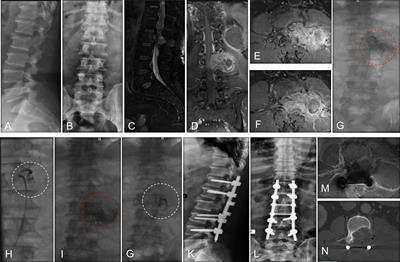

Significance of Pseudomeningocele After Decompressive Surgery for Chiari I Malformation